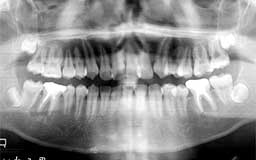

★ Rさん 24歳

若年性歯周疾患や中高年のように明らかな歯槽骨破壊が認められるメインテナンスと違って、

若年者のメインテナンスには虫歯の進行を抑制する効果がより鮮明に認められます。この効果

初診時24歳だったRさんは、几帳面な性格で口腔内清掃状態も良好でしたが、何しろ神経を

とって被せた歯が多いというのが第一印象でした。歯に異常を感じたらすぐ歯医者に行って治

療するといったタイプです。そしてその都度神経をとって被せる治療を繰り返し、24歳にして

すでに6本の神経をとっていました。「神経をとったらロクなことがない」ことは重々承知し

ている歯医者も、患者さんが不都合を感じたときには神経を取らざるを得ない状況であること

が多いからです。萌出してわずか10年そこそこしか経っていない歯の実に1/4近くがすでに抜

髄されて、生涯機能しつづける権利を放棄したに等しい状況だともいえます。ご多分に漏れず、

右下第一大臼歯には根尖病巣があって、しかも通常の根管治療もできない状態でした。やむな

く2本ある根っこうち1本を部分的に抜歯して(ヘミセクションといいます)ブリッジにしま

した。

治療終了後もこれから先どうなるのだろうという不安が付きまとっています。これは私が歯

槽膿漏のメインテナンスをはじめてすでに8年ほど経過したころですが、特に目立った歯槽膿

漏の兆候のないRさんにメインテナンスを勧めるのは若干の抵抗がありました。しかし、本人

の申し出もあって毎月歯石をとるというメインテナンスを始めました。それ以来13年経過して

いますが、不思議なことにそれ以来歯の神経をとるような事態になることは一度もありません。

メインテナンス期間を通して、1〜2年に一度ほどのペースで細かな虫歯をみつけて治療はして

いましたが、基本的には何もしないで13年を無事経過したような印象があります。小学校のこ

ろから10余年間虫歯に悩みつづけたRさんも不思議な思いでメインテナンスを継続されている

ことと思います。

| Rさん 初診時 24歳 女性 清掃状態も良いのにすでに抜髄された歯が6本もあるのが特徴的です |

Rさん 13年後 37歳 初診時の治療以来、ほとんど追加治療することなく経過しています |